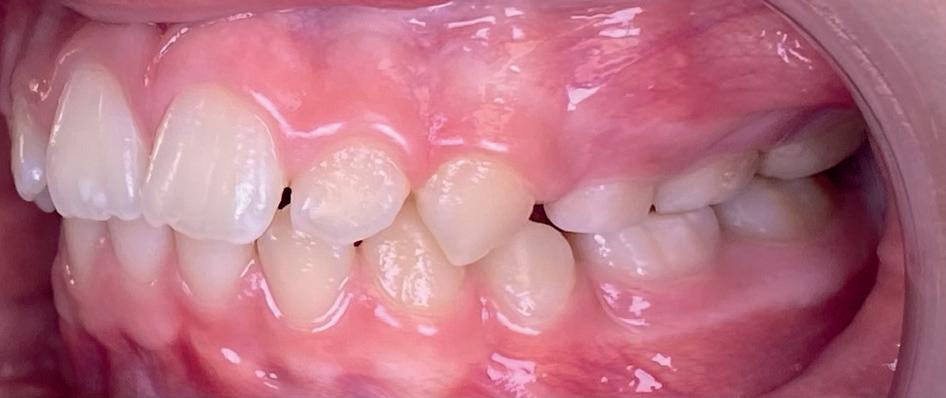

Casus: Blix – Ruimte creëren zonder extracties met D-gainer en Damon Ultima Blix (10 jaar) presenteerde zich met een klasse II-occlusie, smalle boven- en onderkaak en ruimtegebrek voor de doorbraak van de hoektanden en premolaren. Hoewel haar gezicht in balans was, zou zonder behandeling het gebrek aan ruimte toenemen en de diepe beet verder verergeren.

Behandeling in twee fasen

1. D-gainer & verbreding

Om extracties te voorkomen, werd gestart met een D-gainer. Dit is een methode met slotjes en veertjes waarmee de molaren gecontroleerd naar achteren worden verplaatst. Tegelijkertijd werd de tandboog verbreed – zonder buitenboordbeugel.

• Doel: ruimte creëren voor de hoektanden (13/23) zonder premolaren te verwijderen

• Duur: ongeveer 6 maanden

2. Vaste beugel (Damon Ultima)

Na voldoende ruimte werd gestart met de volledige vaste beugel in boven- en onderkaak. Hiermee werden de tandbogen uitgevlakt, de scheefstand gecorrigeerd en de tandbogen verbreed – met behoud van het natuurlijke profiel.

Resultaat

• Klasse I-occlusie

• Harmonieuze lachlijn en verbrede tandbogen

• Geen extracties

• Profiel en gezichtsbalans behouden

Retentie: Vaste spalk boven én onder, aangevuld met een nachtbeugel

“Door ruimte te creëren met een D-gainer in plaats van tanden te trekken, blijft het profiel natuurlijk en ontstaat een bredere, stabiele tandboog.”

voor

Casus in Proces

Patiënt Sonnie presenteerde zich met ernstig ruimtegebrek ter hoogte van de 13 en 44 en een kruisbeet aan de zijde van de 15 en 14. De 13 was ectostematisch gepositioneerd, waardoor extractie aanvankelijk als mogelijke behandeloptie werd overwogen.

Door een combinatie van verbreding en het inzetten van een D-gainer wordt de benodigde ruimte gecreeerd om alle elementen correct in de tandboog te positioneren, waardoor extracties kunnen worden vermeden. De behandeling zal binnen twee jaar worden afgerond; het eindresultaat wordt gedeeld in editie 2 van ons magazine.

Start behandeling

Midden behandeling

Laatste fase